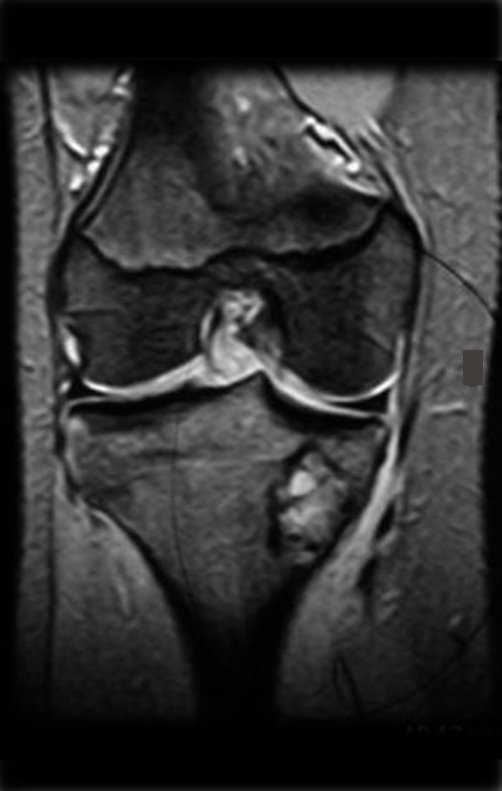

El estudio imagenológico de la lesión puede ser más detallado mediante tomografía (figura 3c), que permite evaluar la erosión de la corteza ósea y la afectación extracortical. La resonancia magnética es importante para definir la extensión del tumor, tanto en la zona medular como extracortical (figuras 4d, 4e y 4f). Este examen también permite evaluar la relación entre el tumor y las partes blandas (músculos, vasos y nervios) y es fundamental para la planificación quirúrgica.

Después de la quimioterapia (preoperatoria) le fueron realizados los estudios de imagen para evaluación clínica de la respuesta a la quimioterapia de inducción y planteamiento quirúrgico (Figura 30 a 38).